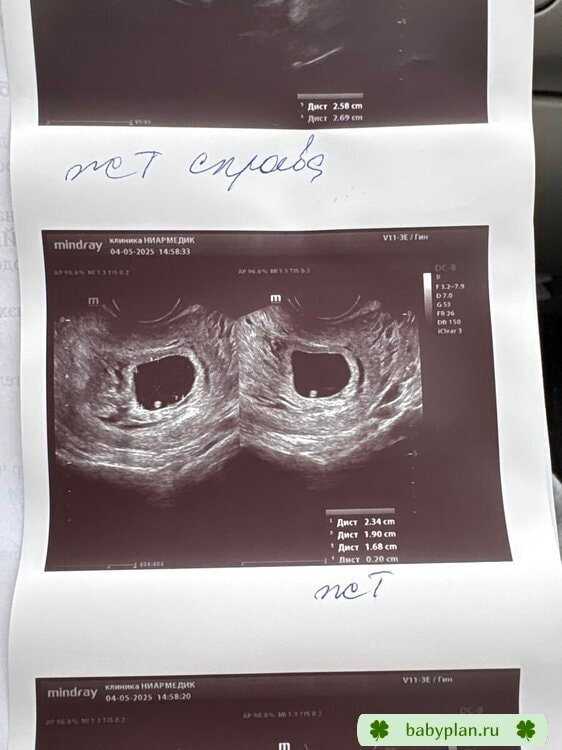

УЗИ, КТГ, доплерПервое узи было в 6.1 по М, увидели ПЯ 15мм, ЖМ 4мм и предположительно эмбрион 5мм (в платной), в ЖК в 6.5 увидели только ПЯ 20мм (узист быстро смотрела, да и мне ничего не показала на экране). Так бывает, что за 4 дня все пропадает?😅 ссылаюсь к тому, что узист в ЖК не очень. Завтра (7.1 по М будет) пойду в платную снова на узи. ХГЧ рос хорошо:

Такая фотка получилась в этот раз